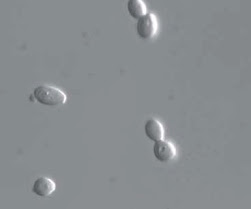

a. Yeast are unicellular organisms which multiply by budding and are characterized by the absence of mycelium. An example is Cryptococcus neoformans.

Candida albicans appears in several morphological forms (blastospores, pseudohyphae, and hyphae). Candidalysin is a cytolytic 31-amino acid α-helical amphipathic peptide produced by the Candida albicans hyphae, and it is crucial in damaging the host cells.